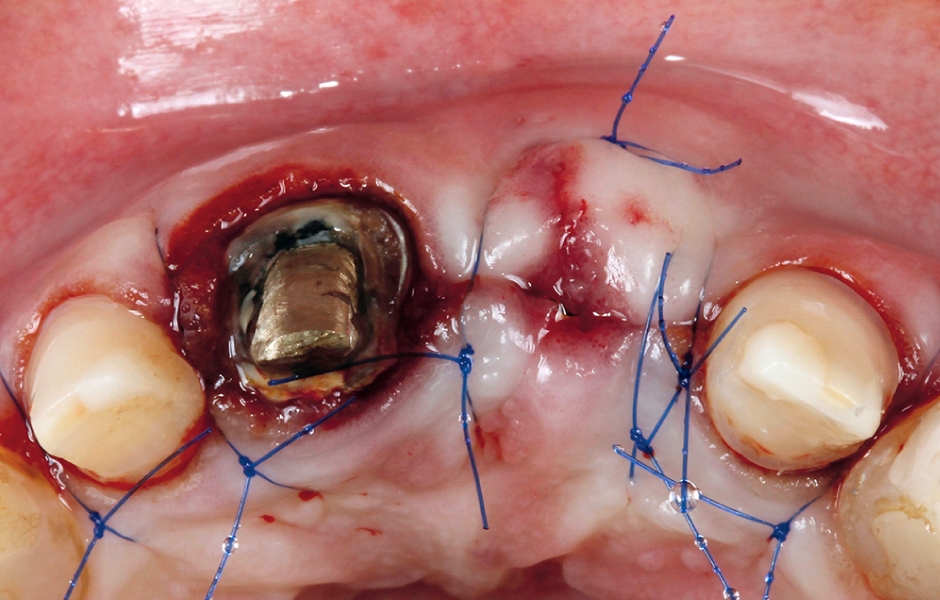

V první fázi byly odstraněny staré náhrady velkých řezáků v horní čelisti a byla zhotovena provizorní pryskyřičná náhrada, kotvená pouze na zubu 11 (obr. 4a). Vzhledem ke klinicky špatnému stavu lůžka implantátu a jeho nevyhovující pozici byl implantát odstraněn (obr. 4b) a byla provedena regenerace kosti v kombinaci s transplantací štěpu pojivových tkání (obr. 4c, d).